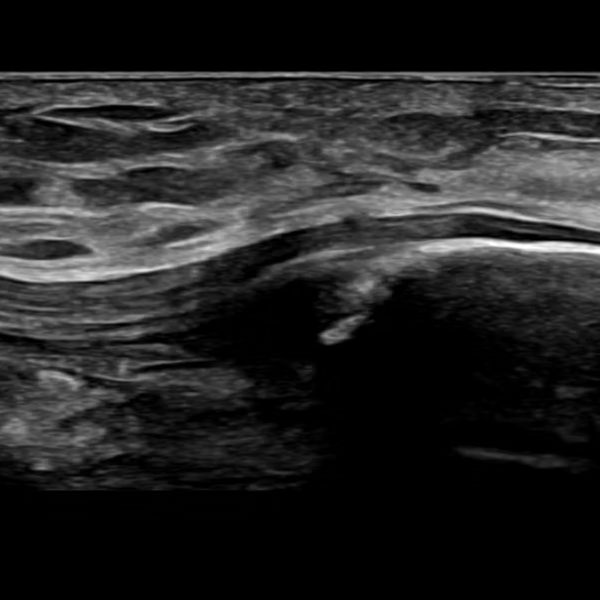

Musculoskeletal ultrasound exam at Mississippi Motion

Musculoskeletal ultrasound uses high-frequency sound waves to produce detailed images of soft tissues. Unlike X-rays or CT scans, ultrasound does not use radiation. A handheld transducer sends sound waves into the body and receives the echoes, creating live, moving images on the screen.

Musculoskeletal ultrasound, Mississippi Motion

Musculoskeletal ultrasound at Mississippi Motion